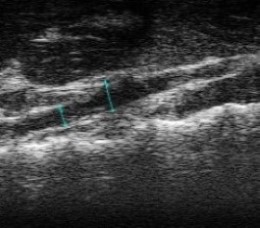

- in vivo VisualSonics Vivo 2100 vascular imaging

Abdominal Echo's performed 24 hours prior to sac using VisualSonics Vivo 2100